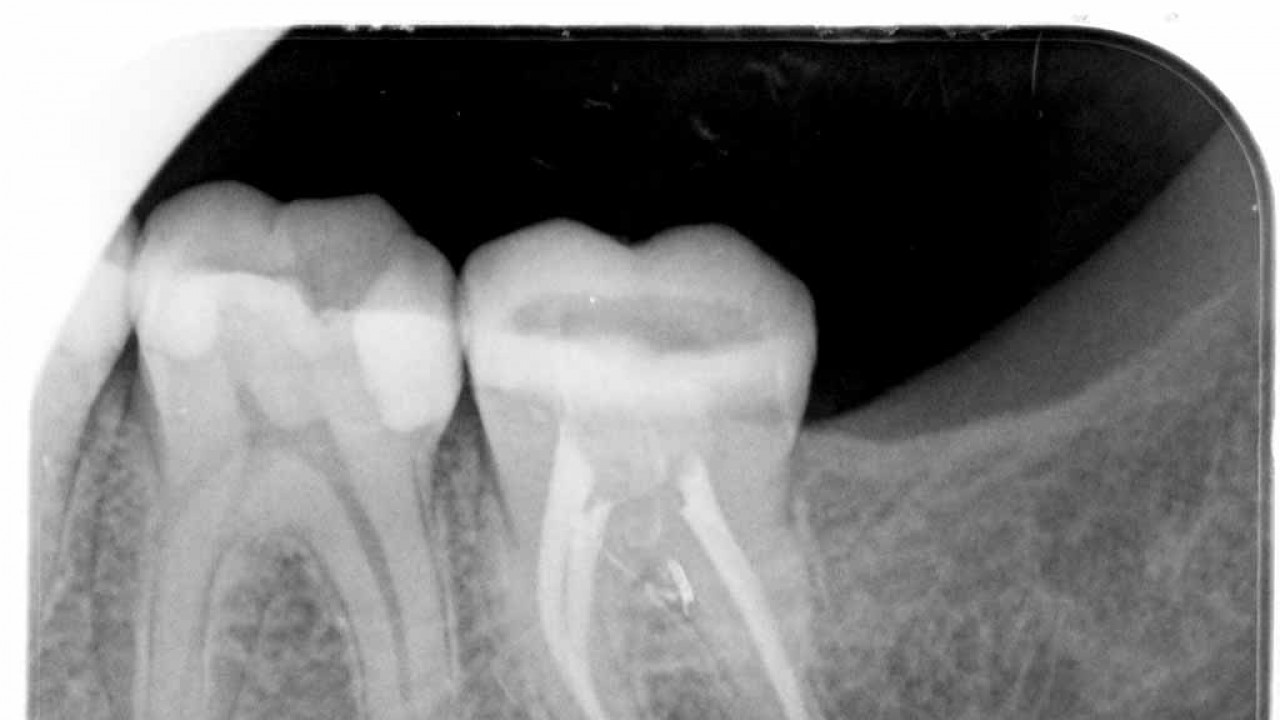

Kanal tedavisi ile ilgili başarıdaki en önemli etmenlerden biri kök kanal boyunun tam doğru olarak belirlenebilmesidir. Doğru belirlenemeyen kanal boyunda çalışıldığı zaman gerekli temizlik ve dezenfeksiyon işlemleri olması gerektiği yapılamaz. Bu türlü tedavilerde ise iyileşme elde edilemez. Eskiden kanal boyu belirleme için sadece filmlerden faydalanılıyordu. Fakat diş ve çevre dokuların anatomisinden de kaynaklı olarak filmler ile bu bilgi tam olarak elde edilememekteydi.

Elektronik apex bulucuları bu sorunu büyük ölçüde çözerek filmlere duyulan ihtiyacı azaltmış, hem daha iyi tedavi yapılmasına olanak sağlamış hem de maruz kalınan radyasyonu azaltmıştır. Bu cihazların kullanımı ile sinirleri dişe girdiği nokta tam olarak tespit edilebilir ve başarılı kanal tedavileri gerçekleştirilebilir.